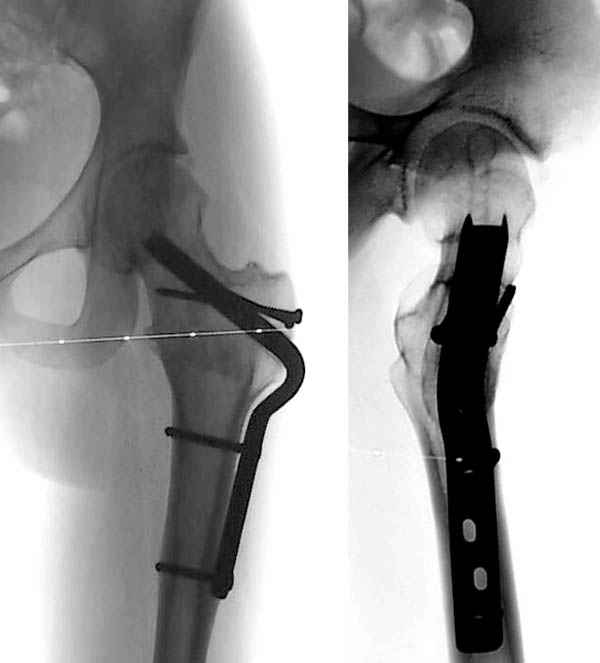

Ребёнок 14 лет. Весом под центнер. Имеющаяся рентгенологическая деформация деформация - на момент поступления. Госпитализирован ребёнок 14 лет. Мальчик, мягко говоря, крупный, гиперстенического типа сложения, ближе к десантнику. Весит 95 кг. Ожирение 2-й степени. Со слов больного - испытывает дискомфорт в области тазобедренного сустава в течение 3-х месяцев. На рентгенограммах - положение дел на момент поступления - конец мая. Укорочение конечности на 1,5 см. Ограничение внутренней ротации. Ходит, едва заметно прихрамывая на больную ногу. Эндокринологический статус находится в стадии обследования. Выполнена рентгенография в стандартных укладках, спиральная КТГ.Ясное дело, головка бедра <ушла> вниз и кзади. Пытающаяся <поймать> её шейка варизировалась и исполнила ретроверсию, создав изгиб во фронтальной плоскости. На рентгеноскопии - подвижность головки не определяется. Мальчик имеет далеко идущие планы на обустройство собственной жизни и образование. Крайне негативно относится к длительной иммобилизации и консервативному лечению. Загодя не согласен со снижением качества жизни в процессе лечения. Мнения коллег относительно дальнейшего лечения разделились. Успешность репозиции головки под наркозом - сомнительная в связи с имеющейся деформацией шейки бедра. Одни склоняются к тактике невмешательства - разгрузка больной конечности, ФЗТ , массаж, и т.д. Предлагают ждать завершения процесса <сползания> головки в условиях полной разгрузки, <тянуть> сустав до эндопротезирования как можно дольше. Другая группа коллег предлагает немедленную стабилизацию головки, что, кажется, правильно. Принимая во внимание анатомическое соотношение головки и шейки бедра, способ остеосинтеза так же вызвал массу споров, не приведших к единому и окончательному мнению. Пока дискуссия остановилась на стабилизации спицами Бека под контролем ЭОП, возможно с применением электродов для проведения электростимуляции слабыми импульсными токами. Техника проведения спиц, однозначно, будет сопряжена с техническими трудностями, обусловленными имеющейся деформацией шейки. Как бы Вы поступили, коллеги, в данной ситуации?Заранее спасибо. И прошу прощения за качество спимков. Буду отправлять их по очереди.

Здравствуйте Данил. По представленным рентгенограммамам и кт срезам Вы имеете дело хронической, стабильной формой ЮЭГБК. Шеечно- эпифизарная деформация выраженная, эпифиз отклонён кзади более чем на 70 градусов, практически до упора в межвертельную ямку, что характеризует её как тяжёлую степень. В выборе метода лечения мы придерживаемся следующей схемы:

Здесь представлен один из случаев остеотомии на шейке после остаточного явления юношеского эпифизиолиза из Flip Trochanteric доступа.